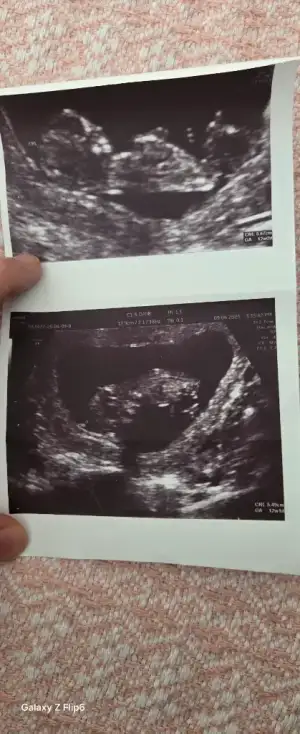

Lütfen banada bakarmısın Pasha22 Pasha22

Vajinal ilk 6 hafta

Ikinci 11 hafta

Eklentiler

• 1000206281.webp

1000206281.webp

8,9 KB · Görüntüleme: 52

• 1000217629.webp

1000217629.webp

15,9 KB · Görüntüleme: 52